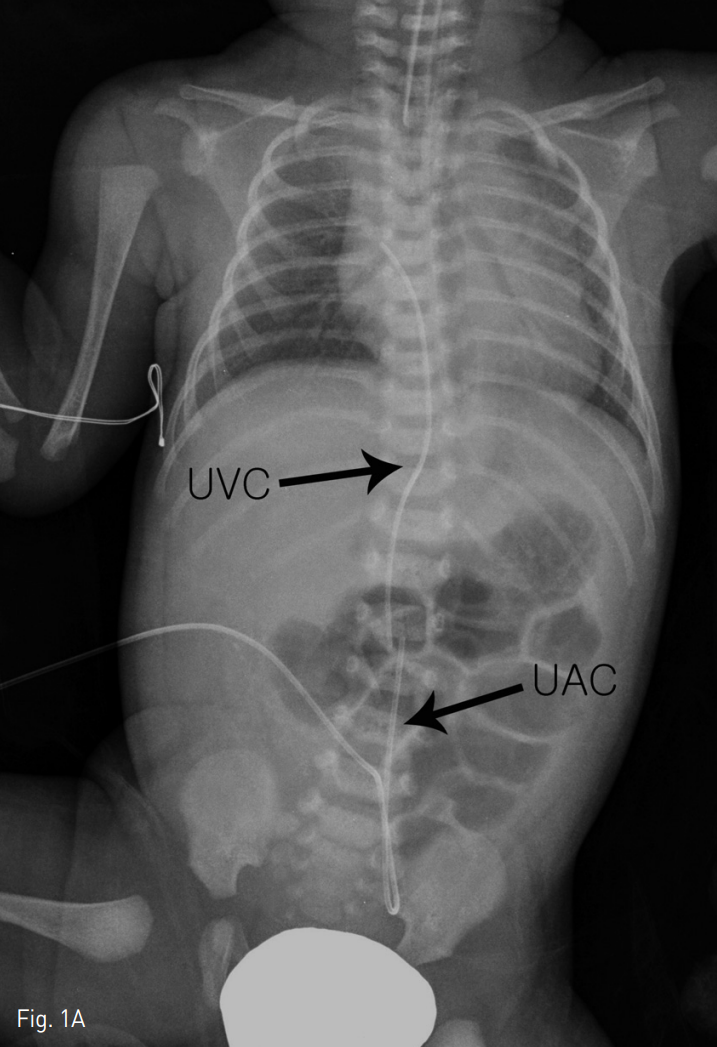

환아는 인터벤션 시술실로 이동하였고 18G 주사침으로 제대정맥을 천자하였으며 조영제를 주입하여 성공적인 천자와 제대정맥관의 위치를 확인하였다. 0.035-inch 유도철사를 넣고 주사침을 5 Fr 소아용 혈관초(Cordis, Miami, FL, USA)로 교체하였다. 이후 10mm의 직경을 가진 Amplatz gooseneck snare kit(EV3, Plymouth, MN, USA)를 제대정맥 내로 주입하였다. 이후 조심스런 여러 번의 시도 후에 제대정맥관의 끝부분을 잡는 것에 성공하였고 천천히 제대정맥 바깥쪽으로 제거하였다 (Fig. 2). 제대정맥관의 성공적인 제거는 투시화면상으로도 확인하였다 (Fig. 3).

Fig. 2

Fluoroscopic image showing retrieval of the broken UVC with a snare wire